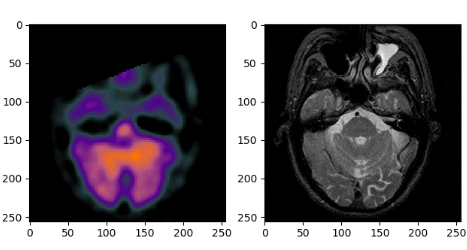

file_name1='test_imgs/spect/1.png' # 这是彩色图片

file_name2='test_imgs/mri/1.png' # 这是灰度图片

fig=plt.figure()

f1 = fig.add_subplot(121)

f2 = fig.add_subplot(122)

f1.imshow(spect)

f2.imshow(mri)

plt.show()